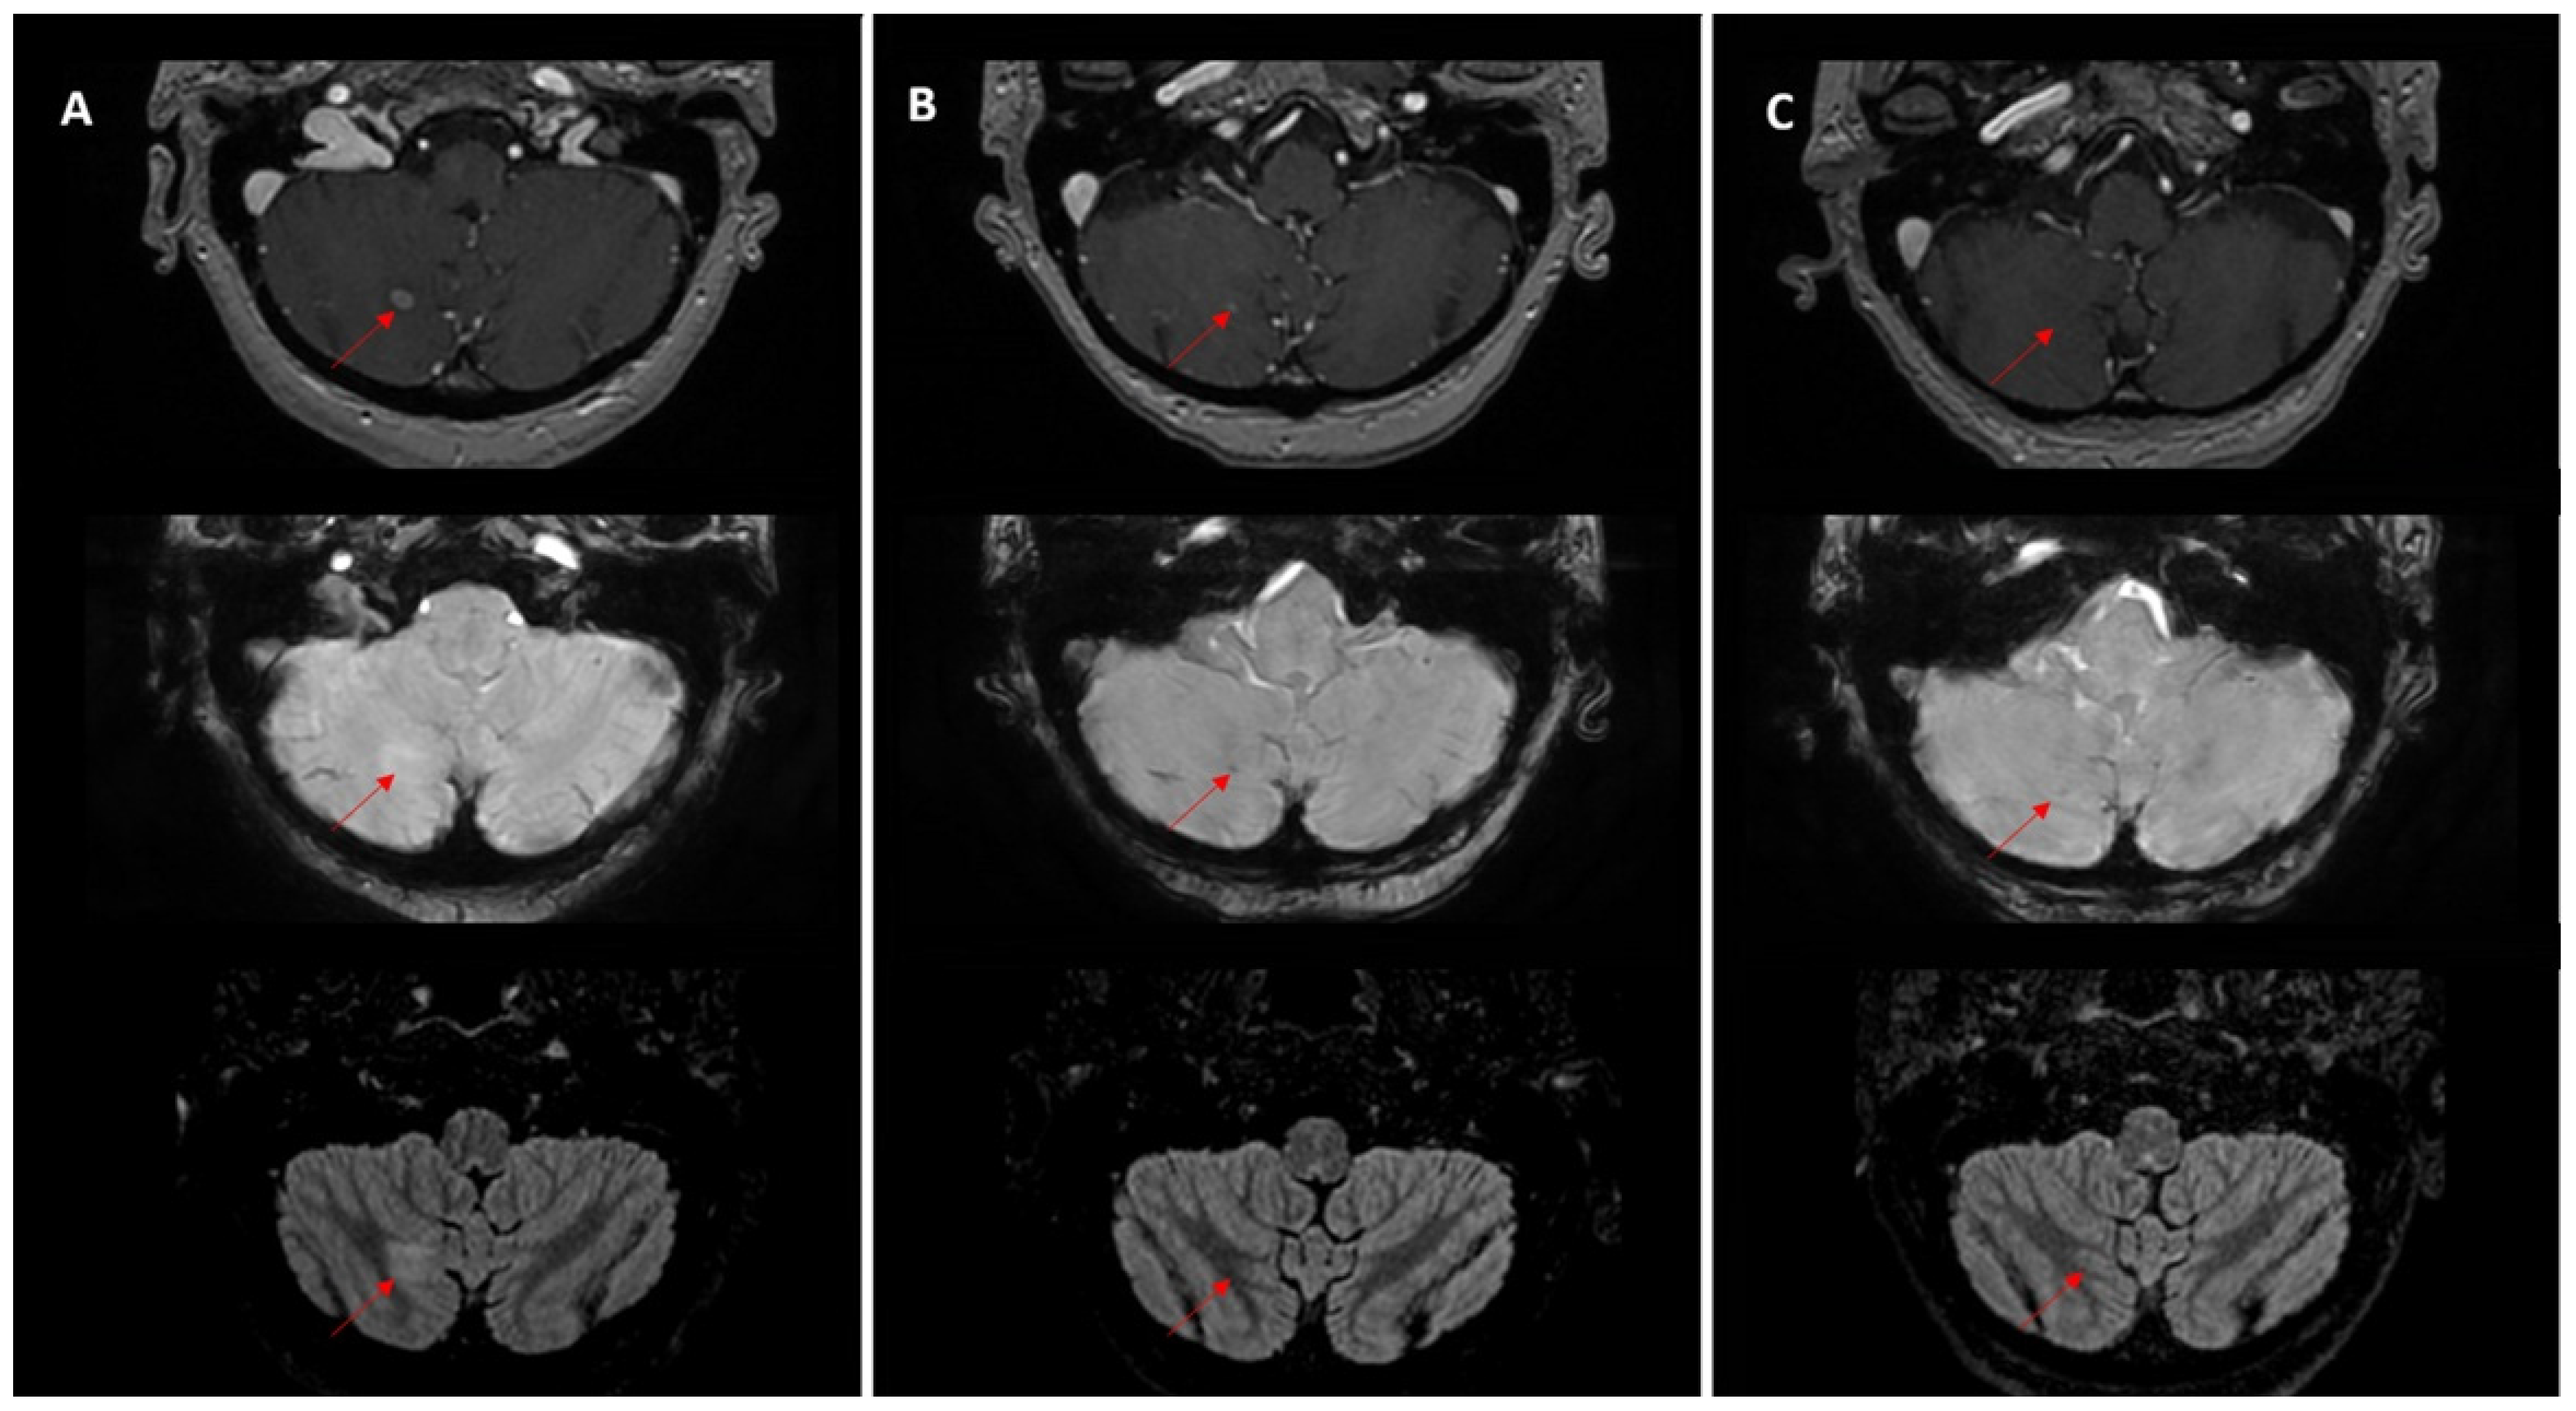

Figure 4. Longitudinal MRI of a left frontal brain metastasis (red arrows) in a patient with lung cancer treated with stereotactic radiotherapy (SRT, 35 Gy/5 fractions). (A) Baseline scan before SRT shows an enhancing lesion. (BD) Post-treatment follow-up demonstrates dimensional increase with irregular, thin margins and persistent enhancement over time.

A subset of monitored lesions, 18.4% (65/354), showed dimensional increase during follow-up. Without histopathologic confirmation or advanced imaging criteria, it is difficult to differentiate true tumor progression from post-treatment effects such as pseudoprogression or radiation necrosis. When reports describe only dimensional increase without noting that the lesion was irradiated (e.g., three or six months earlier), important clinical context is lost, potentially creating interpretative ambiguities. In such cases, post-treatment enlargement may be misclassified as progressive metastatic disease rather than a treatment-related change (Figure 4).